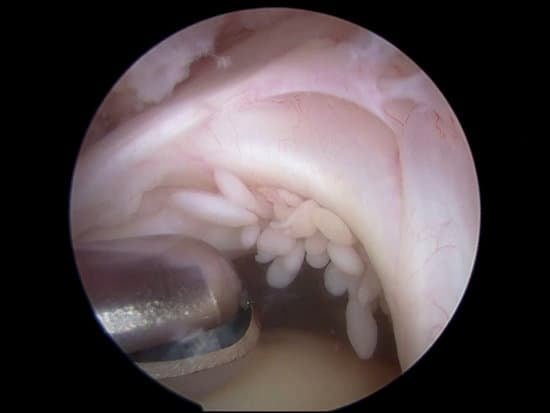

관절경 수술: 작은 절개를 통해 카메라와 도구를 삽입해 회전근개를 복구하는 방법입니다. 이 방법은 회복 시간이 짧고, 흉터가 적은 장점이 있습니다.